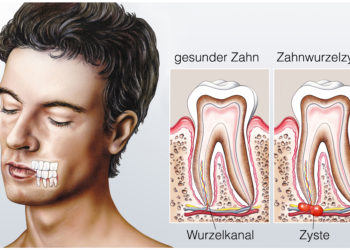

- Zahnzyste – Ursachen und Therapie

- Zysten – Ursachen, Symptome und Therapie